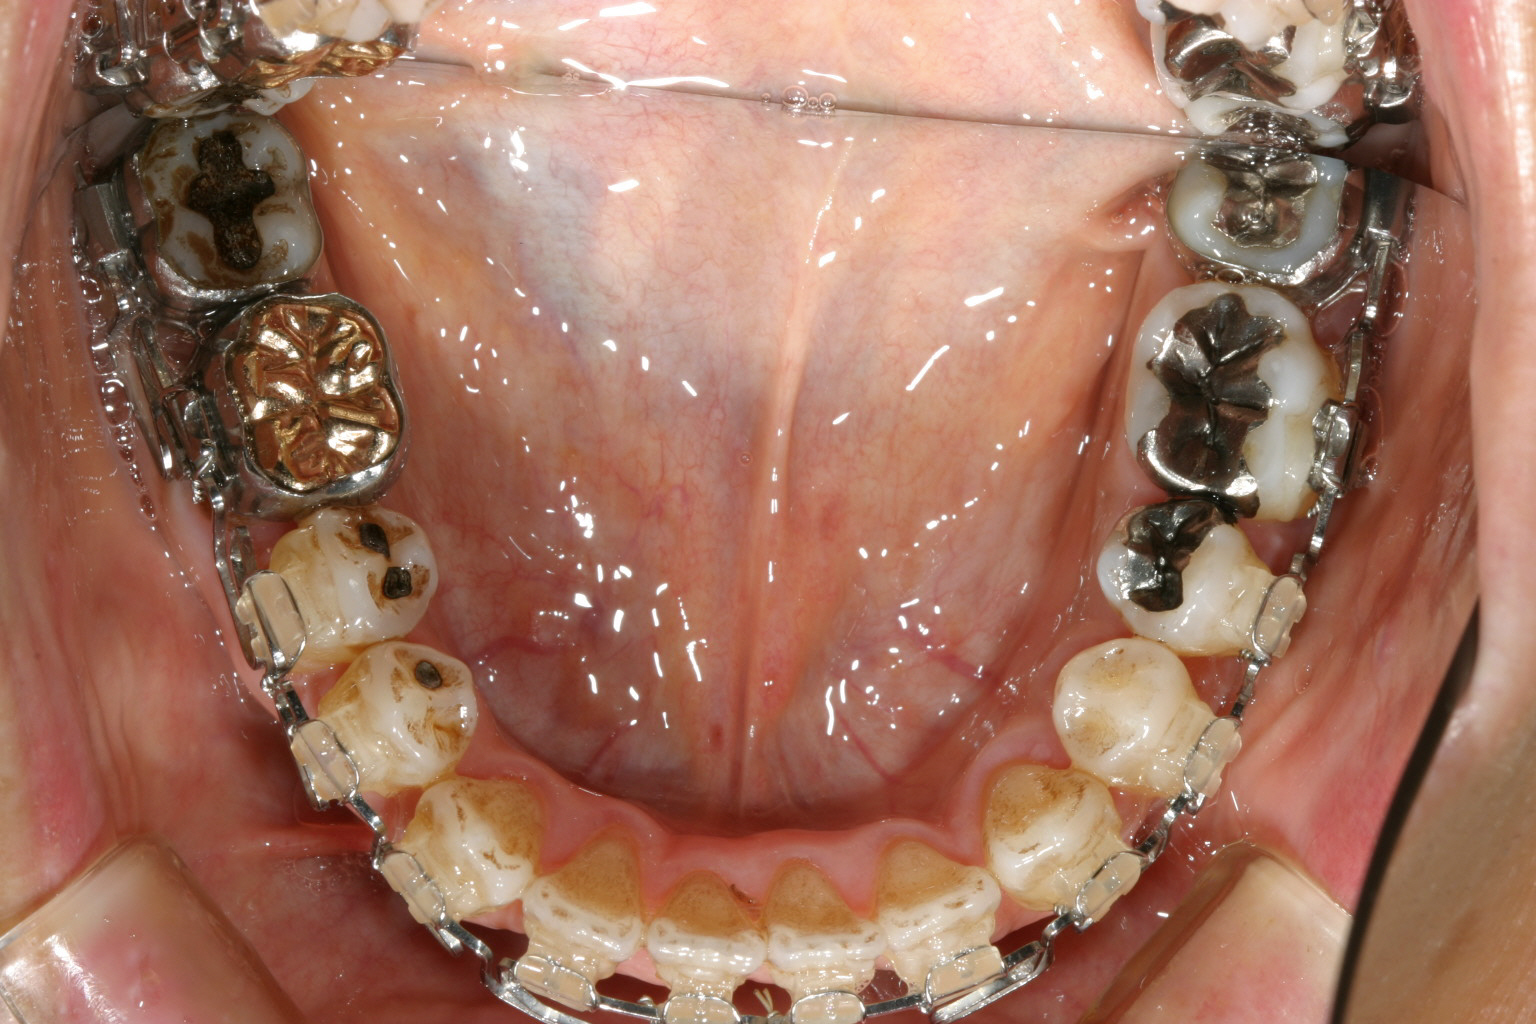

こちらもマリガンワイヤー使用です。 下顎も綺麗になってますね~

下顎マルチループワイヤー、上顎にマルチループワイヤーとマリガンワイヤー使用で殆ど上下切端の隙間も閉じてきました。

綺麗な歯列になりました。

これなら羊羹もパクリと噛めそうです。